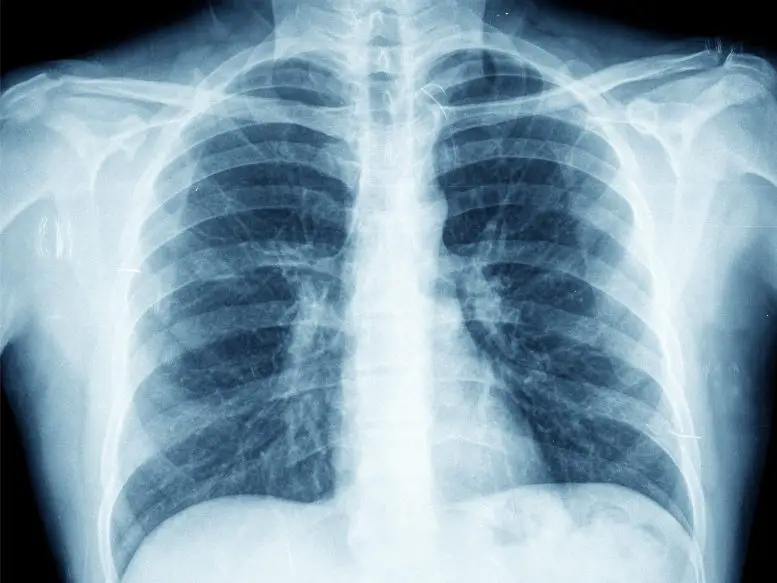

Рентгенография грудной клетки является широко распространенным диагностическим инструментом в медицине. Однако для правильной интерпретации снимков требуется значительная подготовка и опыт. Хотя для помощи рентгенологам в постановке диагноза были разработаны средства искусственного интеллекта, их клиническое применение пока находится на ранней стадии. Д-р Плеснер подчеркивает необходимость дальнейшего тестирования инструментов ИИ в реальных клинических сценариях для определения их истинной диагностической точности.

В ходе исследования было проанализировано 2040 последовательных рентгеновских снимков грудной клетки взрослых, сделанных в течение двух лет в четырех датских больницах в 2020 году. Средний возраст пациентов составил 72 года, а на 32,8% рентгенограмм была выявлена хотя бы одна целевая находка, относящаяся к трем распространенным заболеваниям легких: патологии воздушного пространства, пневмотораксу и плевральному выпоту.